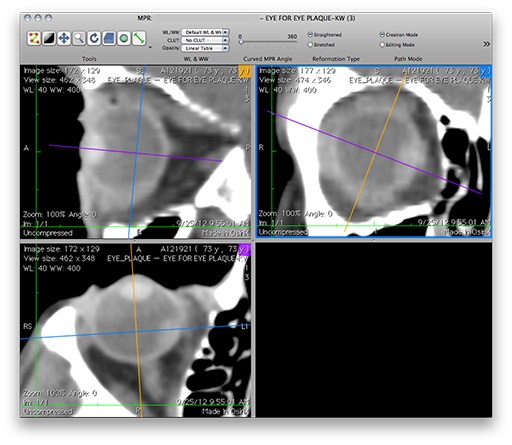

• A new window with 4 panes will appear showing three orthogonal reconstructions and a blank pane.

• Quadrant I: Coronal reconstruction in the upper-right pane.

• Quadrant II: Sagittal reconstruction in the upper-left pane.

• Quadrant III: Axial reconstruction in the lower-left pane.

• Quadrant IV: The lower-right pane is empty.

OsiriX: The 4-pane window

• The image manipulation tools are on the left side of the header section.

OsiriX4Pane.png